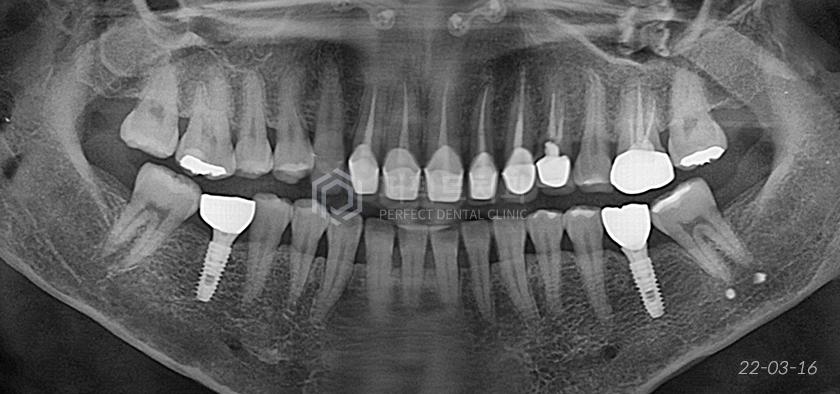

초진당시

치료 전 파노라마 사진을 통해 앞니에 신경치료가 되어있는 것을 알 수 있습니다.

신경치료한 치아를 포함해 앞니 7개에 보철치료가 진행되어있었는데 육안으로 보기에도 잇몸과 치아의 경계가 닳아 있고

잇몸에 염증도 있는 상태였습니다. 심지어 발치까지 필요한 상태...